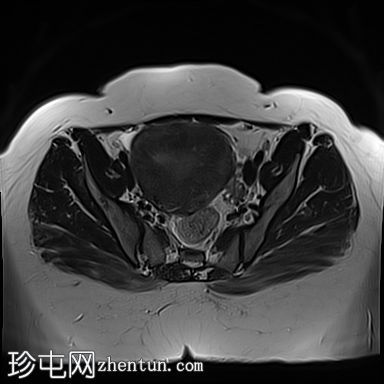

矢状位

T2加权像

子宫前倾且体积增大,交界区呈边界不清、弥漫性对称性增厚。T2加权像和T2脂肪抑制像均显示条纹状高信号,无异常强化或扩散受限。

子宫内膜腔、交界区和外层肌层边界不清。

本病例展示了弥漫性子宫腺肌症的典型MRI特征,包括交界区弥漫性增厚和T2加权像上呈条纹状高信号区域。